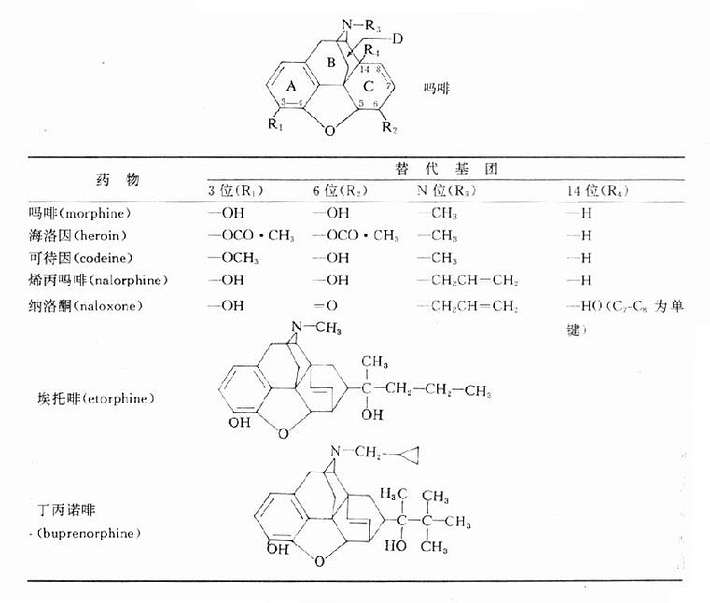

【化学结构及构效关系】 吗啡(morphine)的分子结构由四部分组成:①保留四个双键的氢化菲核(环A、B、C);②与菲核环B相稠合的N-甲基哌啶环;③连接环A与环C的氧桥;④环A上的一个酚羟基与环C上的醇羟基。酚羟基氢原子被甲基取代,则镇痛作用减弱(如可待因);叔胺氮被烯丙基取代,则不仅镇痛作用减弱,而且成为吗啡的拮抗药,如烯丙吗啡和纳洛酮(表18-1)。

表18-1吗啡及其衍生物的化学结构